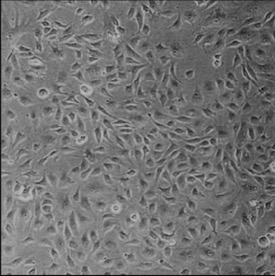

Deep-learning models have been successful in biomedical image segmentation. To generalize for real-world deployment, test-time augmentation (TTA) methods are often used to transform the test image into different versions that are hopefully closer to the training domain. Unfortunately, due to the vast diversity of instance scale and image styles, many augmented test images produce undesirable results, thus lowering the overall performance. This work proposes a new TTA framework, S$^3$-TTA, which selects the suitable image scale and style for each test image based on a transformation consistency metric. In addition, S$^3$-TTA constructs an end-to-end augmentation-segmentation joint-training pipeline to ensure a task-oriented augmentation. On public benchmarks for cell and lung segmentation, S$^3$-TTA demonstrates improvements over the prior art by 3.4% and 1.3%, respectively, by simply augmenting the input data in testing phase.